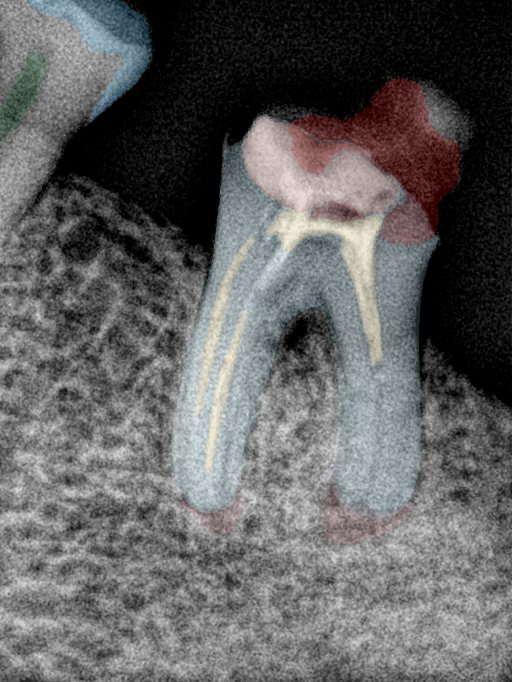

CR/DR 牙齿分割阶段记录

当前进展

- 完成了 CR/DR 牙齿相关分割训练

- 当前结果已经达到阶段预期,但仍有细节问题需要继续处理

相关测试

遇到的问题

- 训练过程中出现过 mask 下移问题

- 部分结果会出现 box 填充异常

- mask 边缘仍然有比较明显的锯齿感

参考

第二版算法问题测试

Updated: 2026-04-13(更新日期)

| 第一版 | 第二版 | 是否解决 | |

|---|---|---|---|

![]() | ![]() ![]() 边角识别有问题 龋齿识别不全 牙髓识别不全 | ![]() | 解决 |

![]() | ![]() 边角识别有问题 识别信息有误 自查(牙冠识别不全) | ![]() | 解决 |

![]() | ![]() ![]() 边角识别有误 大范围填充识别遗漏 | ![]() | 解决 |

![]() | ![]() 识别信息不全 | ![]() | 解决 |

![]() | ![]() ![]() 边角问题 牙胶识别不全 牙冠识别不全 | ![]() | 解决 |

![]() 换图片 | ![]() | ![]() 牙冠部分稍微白了一些就识别成小范围修补,部分判断异常 | 部分解决,修复类略敏感,牙冠部分稍微白了一些就识别成小范围修补,部分判断异常。 |

![]() | ![]() ![]() 牙冠识别不全 牙髓不全 根尖炎龋齿识别有误 | ![]() | 解决 |

![]() | ![]() | ![]() | 解决 |

![]() 换图片 | ![]() | ![]() | 解决 |

![]() | ![]() 牙冠识别有误 | ![]() | 解决 |

![]() 换图片 | ![]() ![]() 边角识别有误 | ![]() 修复类敏感 | 部分解决,图像过白,导致修复类判断异常。 |

![]() 换图片 | ![]() 牙冠识别不全 | ![]() 修复类敏感 | 部分解决,图像过白,导致修复类判断异常 |

结论:修复类出现了不鲁棒的情况,后续需要加入轮廓的扩充数据进行增强。